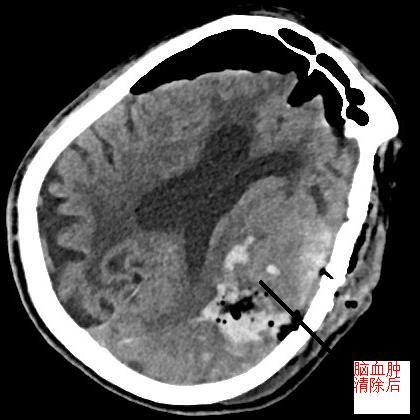

? ? ? 患者李大爺,83歲,走路的時(shí)候突然不能言語、四肢乏力,隨即出現(xiàn)昏迷,家人緊急送往我院急診科就醫(yī)。經(jīng)頭顱CT檢查,提示左側(cè)額頂葉、左側(cè)卵中、圓中心大面積腦出血,腦疝形成,腦出血量大,顱內(nèi)壓力高,需緊急清除腦內(nèi)血腫??紤]到患者年齡高、體質(zhì)差、手術(shù)風(fēng)險(xiǎn)高,我院神經(jīng)外科立即與福醫(yī)大附二院神經(jīng)外科當(dāng)班專家研討病情,根據(jù)患者實(shí)際情況,討論決定使用微創(chuàng)治療,擬給予神經(jīng)內(nèi)鏡下行腦內(nèi)血腫清除。在征得家屬知情同意后,立即進(jìn)行手術(shù),手術(shù)順利。術(shù)后,復(fù)查頭顱CT,發(fā)現(xiàn)腦內(nèi)血腫大部分已清除,顱內(nèi)壓明顯下降,偏移的腦中線較之前有恢復(fù),患者意識障礙得到較大改善,病情相對穩(wěn)定,后續(xù)繼續(xù)觀察治療。

治前VS治療后? ? ? ? ? ?